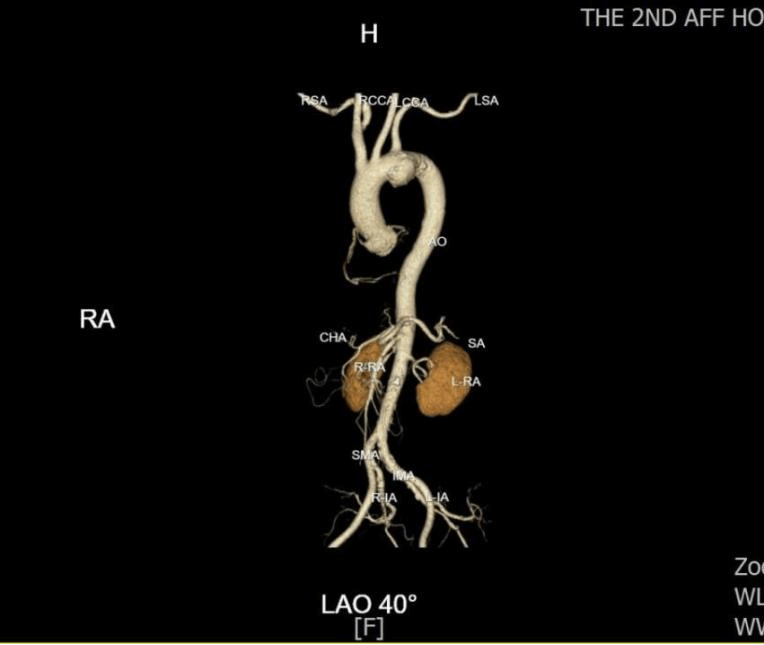

邓捷主任团队反复研判影像后发现,吴大叔的动脉瘤已超出常规 B 型夹层介入范围,若按传统方案,要么牺牲分支血管血供,要么面临 30% 以上的开胸手术并发症风险。“必须为他量身定制方案。” 邓捷主任提出创新思路:Castor 单分支支架锚定左颈总动脉 + 体外开窗重建左锁骨下动脉,既隔绝动脉瘤,又保住脑部与上肢供血。这套方案的关键在 “精准”—— 体外开窗的大小、位置需与血管开口完全匹配,误差超 1 毫米就可能导致内漏或血管闭塞。“邓主任拿着 CTA 图量了又量,连血管夹角都算到小数点后,还加班细化手术流程。” 吴大叔后来从护士口中得知,为确保万无一失,团队还专门调取了国内外 20 余例类似手术文献进行参考。

吴大叔回忆,术前多学科会诊(MDT)时,麻醉、心外、血管外、重症医学科专家逐一敲定细节:从术前评估到应急手术预案,甚至细化到导丝通过血管的路径。手术当天,邓捷主任带领刘小军、韩婕、张恒医生团队身着 30 斤铅衣,在 DSA 设备引导下精准操作:先将定制支架接入左颈总动脉,再以支架为 “坐标” 体外开窗,最后植入左锁骨下动脉支架。“最紧张的是造影那一刻,看到血管通了、瘤子被隔绝,大家才松了口气。” 主治医师刘小军说,整场手术耗时 2 小时,全程无大出血、无血管损伤。术后第 2天,吴大叔就能自主活动肢体;术后第三天,各项指标正常,顺利出院。“原以为要躺半个月,现在能买菜做饭,跟没生病一样!” 出院时,他特意给邓捷主任团队鞠了一躬。